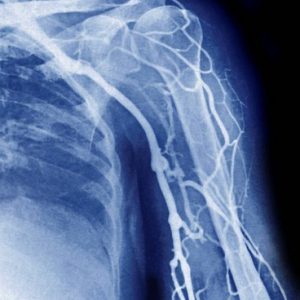

В остальных участках венозного русла (верхние конечности, грудная клетка) патологические процессы достаточно ярко проявляются клинически, легко диагностируются с помощью допплерографии и дуплексного сканирования сосудов, поэтому флебография при тромбозе, к примеру, подключичного или подмышечного венозных сегментов применяется редко, в основном с целью определения объема оперативного вмешательства. На некоторых нюансах флебографии есть смысл остановиться подробнее.

пример нацеленного введения рентеноконтрастного вещества